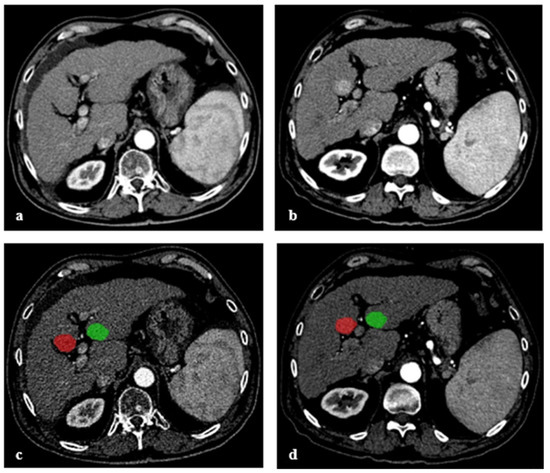

2.3. Image Segmentation